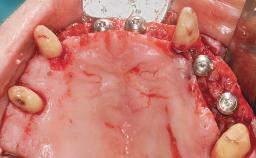

Conventional Loading of Eight Implants in the Maxilla and Final Restoration with a Full-Arch Gold-Ceramic FDP

A 35-year-old Caucasian female presenting with advanced periodontal disease involving both the maxillary and the mandibular dentition was referred for evaluation. The patient, a non-smoker in good general health, requested treatment for recurrent periodontal abscesses, tooth mobility, and discomfort during chewing, as well as restoration of her missing teeth with a fixed prosthesis to improve mastication and esthetics. All residual maxillary teeth exhibited plaque deposits, deep pockets, bleeding on probing, and class III mobility and were evaluated as hopeless. All residual mandibular teeth except tooth 37 could be maintained after periodontal therapy.

# of Implants 8

Type of Implants One-Piece